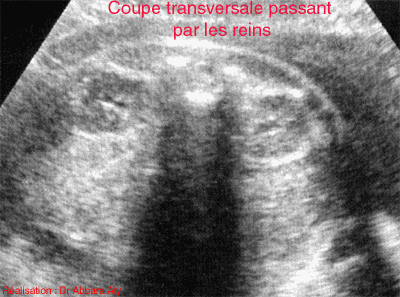

Coupe transversale passant par

les reins fœtaux à 39 SA